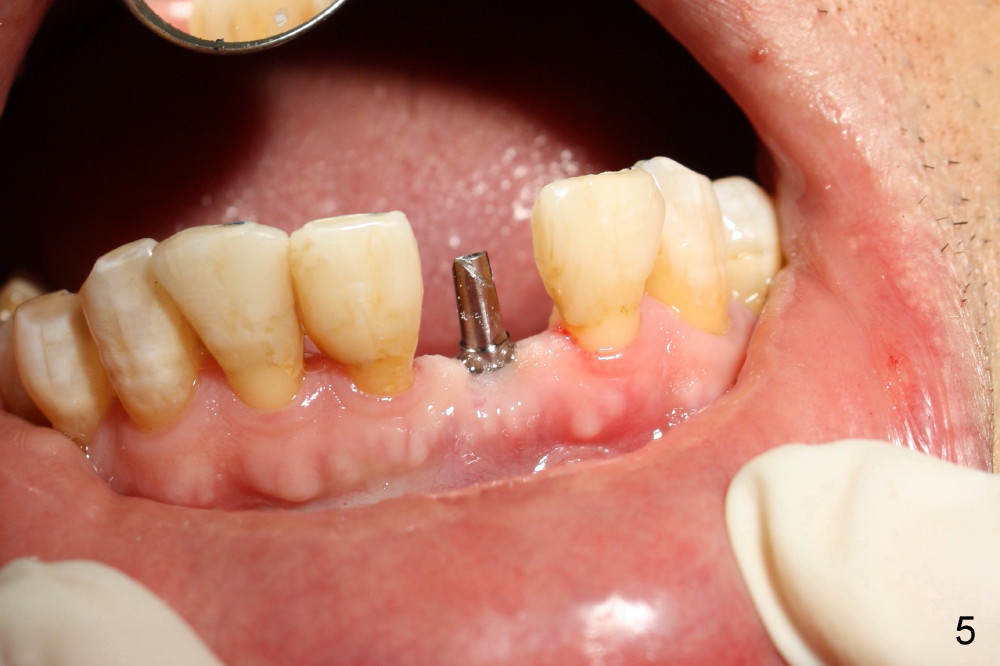

A 3x17 mm one piece implant is planned. Osteotomy is created by a 1.5 mm pilot drill at the depth of 14 mm without incision (Fig.2); it is close to a neighboring incisor. The trajectory of the osteotomy is intended to be changed (Fig.3 red) without success (white, 17 mm deep). With measurement and calculation, the 3x17 mm implant is not expected to touch the root of the adjoining tooth. In fact it is fine with insertion torque between 50-60 Ncm (Fig.4). Without incision, the papillae appear to form immediately following implantation (Fig.5). With adjustment of the abutment (Fig.6), an immediate provisional is fabricated (Fig.7).

Fig.10,11 show 7 day follow up. The permanent crown is seated 4.5 months postop (Fig.12). Minimal bone resorption occurs at the crest 4 months postop (Fig.13), which is most likely associated with conservative approach (flapless). The patient returns for follow up 2.5 months post cementation (Fig.14,15). The implant remains in the bone 4 years post cementation (Fig.16 CT coronal section; lingual thread exposure, corresponding to preop defect in Fig.1). There is mild coronal bone resorption 5 years 4 months post cementation (Fig.17).